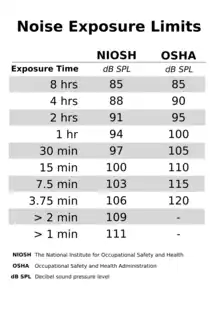

While the standards differ moderately in levels of intensity and duration of exposure considered safe, some guidelines can be derived.[Note 2]

The safe amount of exposure is reduced by a factor of 2 for every exchange rate (3 dB for NIOSH standard or 5 dB for OSHA standard) increase in SPL. For example, the safe daily exposure amount at 85 dB (90 dB for OSHA) is 8 hours, while the safe exposure at 94 dB(A) (nightclub level) is only 1 hour. Noise trauma can also cause a reversible hearing loss, called a temporary threshold shift. This typically occurs in individuals who are exposed to gunfire or firecrackers, and hear ringing in their ears after the event (tinnitus).